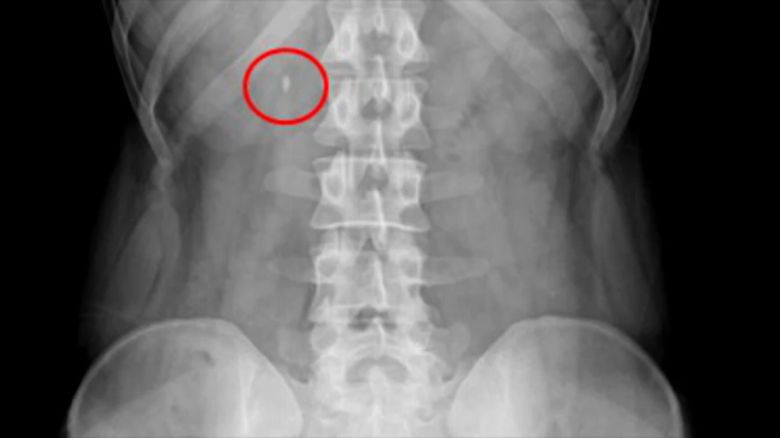

▲ 요로결석 엑스레이

이 기술은 조영제 투여 없이 촬영한 복부 CT 영상을 인공지능 알고리즘으로 분석해 요로결석이 의심되는 부위의 유무, 크기, 위치 정보를 의료진에게 제공하는 역할을 합니다.

쉽게 말해 AI가 먼저 CT 영상을 샅샅이 훑어보고 '이곳에 이만한 크기의 결석으로 의심되는 부분이 있다'고 표시해주는 것입니다.